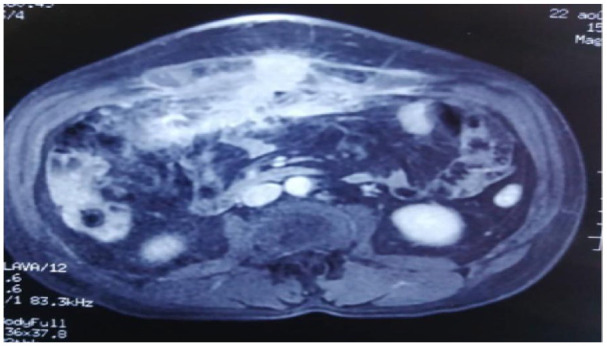

Actinomycosis is a rare chronic granulomatous infection caused by Actinomyces species. We report the case of a 47-year-old man with no previous medical history, who presented with a slowly growing abdominal mass extending to the abdominal wall, initially mimicking a malignant tumor. A diagnosis of an Actinomyces abscess was confirmed through surgical resection and histopathological examination. This case is presented to highlight the morphological characteristics and emphasize the diagnostic difficulties of this disease.